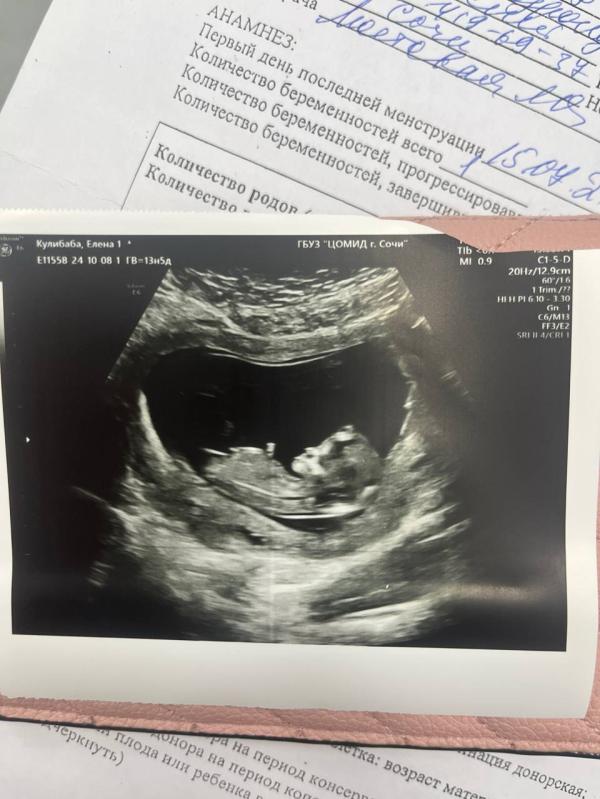

Впереди был первый скрининг. Шла на него вся на нервах, боялась, что может пойти что-то не так.

Врач была очень доброй. Скрининг прошел отлично, и мне даже сказали предварительно пол ребенка- девочка! Каким счастливым был мой муж. С самой первой встречи мы мечтали о девочке.

Через пару дней пришли результаты анализа по скринингу - все хорошо, отклонений нет. Я успокоилась, и начала жить дальше.

Первое фото это получается 6 октября , почти 14 недель.